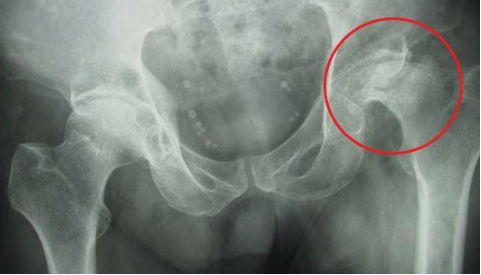

Hoại tử khớp háng khi tiêm corticoid chữa ngứa đầu

Sau 10 ngày liên tục tiêm thuốc chữa ngứa da đầu, anh Sinh thấy mặt phù, da sạm đen, mỏi mệt, mụn trứng cá nổi khắp người.